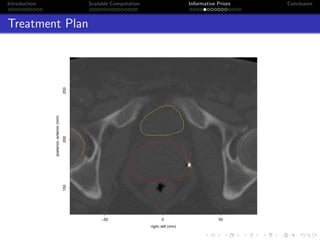

Treatment Plan

−50 0 50

150200250

right−left (mm)

posterior−anterior(mm)